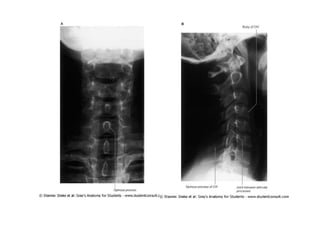

Rx ortostático AP - Pré-

operatório

Fonte: Portal da SBC – casos clínicos

Radiografia

Ortostática de Perfil –

Pré operatória